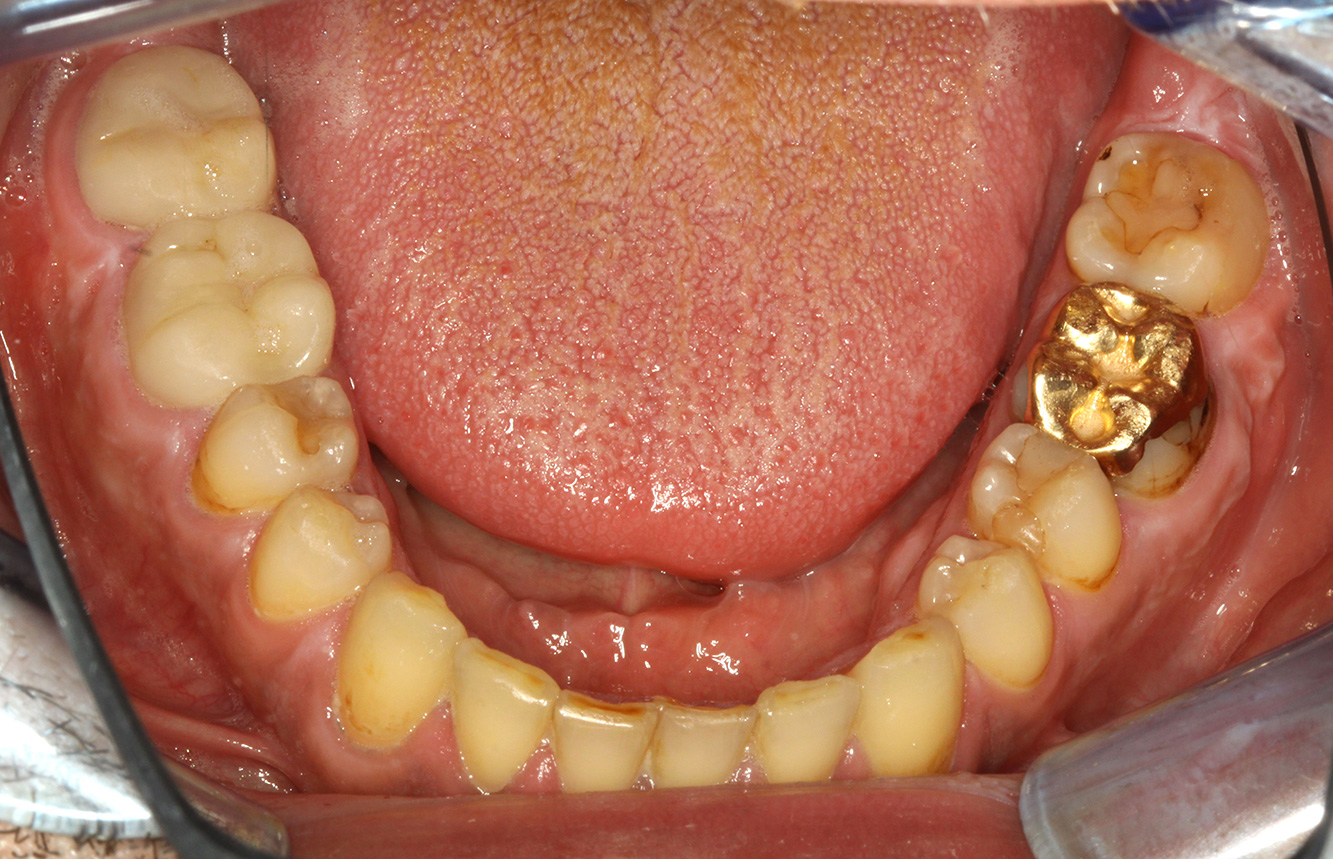

Patientenfälle nach IPCUm das Zusammenspiel der für den IPC definierten Bedarfs- und Risikofaktoren sowie die Auswirkungen einzelner Faktoren zu illustrieren, dienen nachstehende Fallbeispiele*. Die mundgesunde DiabetikerinEine 51-jährige mundgesunde Diabetikerin stellt sich zur Präventionssitzung vor. Die Blutzuckerwerte sind stabil bei einem HbA1c = 6,2%, folglich gilt sie mit dem entsprechenden Medikament Metformin (Antidiabetikum) als suffizient eingestellt. Die Patientin hat keine bestehenden Versorgungen oder orale Vorerkrankungen. Anhand der aktuellen Befunde lässt sich eine Gingivitis bei sonst stabilem parodontalem Zustand (Stage II, Grad B) feststellen. mehr Infos Fallpräsentation: Management komplexer ZahnprothetikEs ist längst bekannt, dass Mundgesundheit und Allgemeingesundheit in direktem Zusammenhang stehen und einen zum Teil bidirektionalen Einfluss aufeinander haben. Die Berücksichtigung beider Faktoren sind bei der Planung der oralen Prävention und Therapie der Patienten in der Zahnarztpraxis unabdingbar. Dabei ist oberstes Ziel, die Gesundheit und die Lebensqualität der Patienten sowohl aus zahnmedizinischer -und medizinischer Sicht zu erhalten. mehr Infos Der (mund)-gesunde Patient mit ImplantatenDer 55-jährige Patient gibt in der Anamnese an, keine Allgemeinerkrankungen zu haben und keine Medikamente einzunehmen. Die Lebensgewohnheiten des Patienten sind ebenfalls unauffällig. Der Patient hat einige zahnärztliche Restaurationen und zwei Implantate (2. und 4. Quadrant). Anhand der aktuellen Befunde lässt sich eine Gingivitis bei stabilem parodontalen Zustand am reduzierten Parodont (Stadium III, Grad A) feststellen. mehr Infos Der gesunde Patient mit parodontaler Vorerkrankung & PeriimplantitisEin 52-jähriger Patient stellt sich zur Präventionssitzung vor. Der Patient hat keine Allgemeinerkrankungen und nimmt keine Medikamente ein. Er hat verschiedene zahnärztliche Versorgungen und zudem zwei aktive kariöse Läsionen. Außerdem verfügt der Patient über vier Implantate (2., 3. und 4. Quadrant). Es zeigt sich eine parodontale Vorerkrankung (Stadium IV, Grad B). Derzeit herrschen stabile parodontale Verhältnisse, lediglich am Implantat regio 36 zeigen sich Sondierungstiefen (ST) von 5 mm. Zudem lässt sich eine Gingivitis feststellen. mehr Infos Der Diabetiker mit ParodontitisDieser Fallbericht eines 52-jährigen Mannes mit Typ-2-Diabetes und Parodontitis hebt hervor, wie durch individuelle Vorsorgemaßnahmen, die Gesundheit des Zahnhalteapparates erhalten bzw. das Fortschreiten der Erkrankung kontrolliert werden kann. mehr Infos Der 28-jährige Raucher mit ZahnerosionenDieser Fallbericht eines 28-jährigen Rauchers mit Zahnerosionen zeigt die Bedeutung personalisierter Patientenprofile. Er unterstreicht die Notwendigkeit, sowohl die Mundgesundheit als auch die allgemeine Gesundheit zu berücksichtigen, um Erkrankungen der Zähne bzw. des Zahnhalteapparates effektiv zu verhindern. mehr Infos Der Endokarditis-Patient mit aktiven KariesläsionenDer Patient ist 39 Jahre mit Z.n. Herzklappenersatz wegen Klappenfehlers und Endokarditis. Als Antikoagulans (Gerinnungshemmer) wird regelmäßig ASS 100 eingenommen. Aus dem Bereich Lebensstil ist die Ernährungsweise als kariesfördernd einzustufen, da mit hoher Regelmäßigkeit zuckerhaltige Lebensmittel sowie sechs bis sieben Mahlzeiten täglich verzehrt werden. Die Mundgesundheit des Patienten zeigt ein mittleres Kariesrisiko mit aktiven Läsionen. Das Parodontitisrisiko ist niedrig, es besteht eine Gingivitis. Es ergeben sich folgende Empfehlungen für die Prophylaxebehandlung. mehr Infos Die gesunde Patientin mit parodontaler VorerkrankungDie 68-jährige Patientin hat keine zahnmedizinisch relevanten allgemeingesundheitlichen Vorerkrankungen oder Medikation, auch aus dem Lebensstil ergibt sich kein besonderes Risiko. Die Patientin hat zwei Implantate (3. Quadrant, seit fünf Jahren) sowie eine parodontale Vorerkrankung (Parodontitis Stadium IV, Grad B) mit Zahnverlust. Derzeit zeigen sich stabile parodontale Verhältnisse. Für die Prophylaxesitzung ergeben sich vier Empfehlungen in den Bereichen Anamnese/Befund, Motivation/Instruktion, der Wahl der geeigneten Instrumente und für Resümee/Folgetermin. mehr Infos

NIWOP – No Implantology without PeriodontologyDer Transplantationspatient mit GingivawucherungenEin 71-jähriger Patient mit Z.n. Nierentransplantation und Hypertonie (Bluthochdruck) stellt sich vor. Bedingt durch die Krankengeschichte ist eine Dauermedikation mit Cyclosporin, zur Unterdrückung der Immunabwehr, und Amlodipin, zur Blutdrucksenkung, erforderlich. Außerdem berichtet der Patient über empfindliches Zahnfleisch und Zahnfleischbluten. Aus mundgesundheitlicher Sicht zeigt sich ein saniertes Gebiss mit acht fehlenden Zähnen, ausgeprägte Gingivawucherungen, eine Parodontitis Stadium II, Grad B mit aktiven Taschen und eine initiale Wurzelkaries an Zahn 22. In der Kariesrisikoabschätzung wird ein mittleres Kariesrisiko (API 60) festgestellt. Für die Prophylaxesitzung lassen sich folgende Behandlungsempfehlungen ableiten. mehr Infos * mit freundlicher Genehmigung von Dr. G. Schmalz und Prof. Dr. D. Ziebolz MSc. Download AreaProxeo Produkte